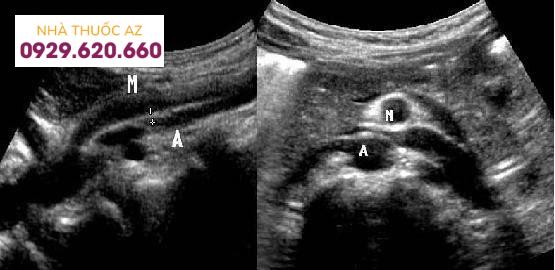

Đo khoảng cách giữa ĐMTTT và ĐM chủ bụng. A, đo được 3.8 mm. B, khoảng cách 9 mm. Nguồn : Birsen Unal et al. Superior mesenteric artery syndrome: CT and ultrasonography findings. Diagn Interv Radiol 2005; 11:91

Mặt cắt dọc và ngang trên siêu âm của bệnh nhân này cho thấy hẹp góc và khoảng cách ĐMTTT và ĐM chủ bụng. Nguồn: Usman Javaid, A.R. Mustafawi, Munir ahmad. The Superior Mesenteric Artery Syndrome (SMAS): Is it really a diagnostic dilemma? Annals of Pediatric Surgery Vol 5, No 3, July 2009, PP 206